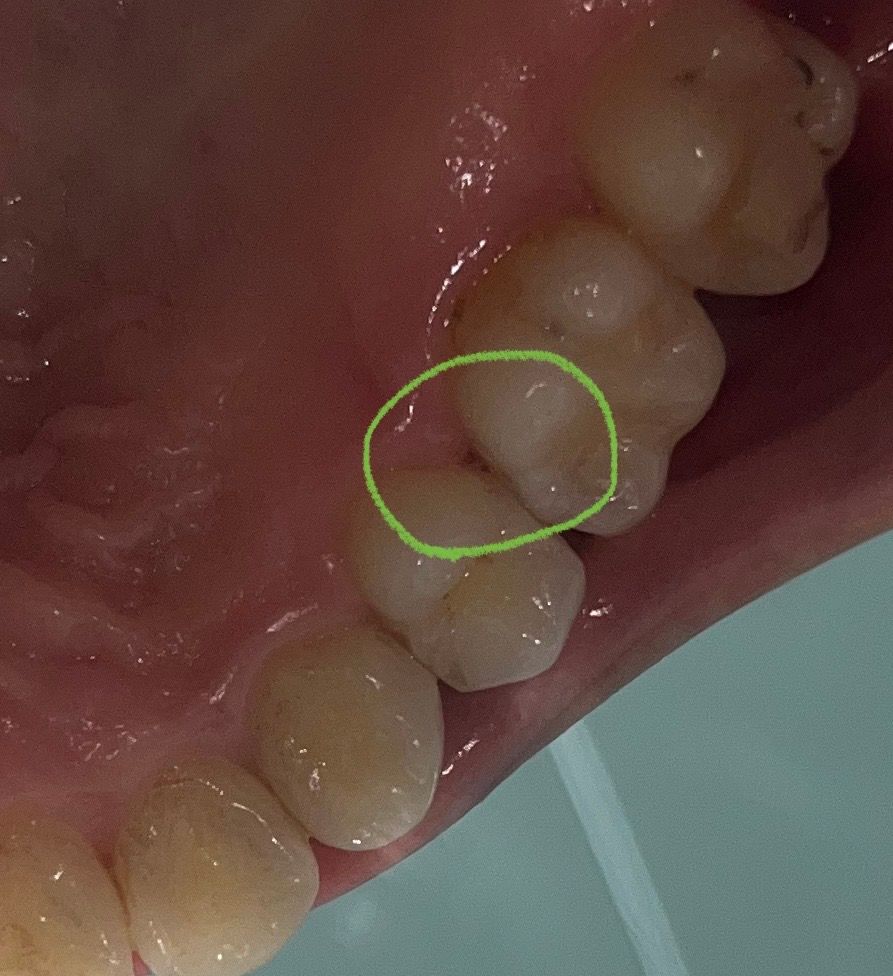

안녕하세요. 어금니와 작은 어금니 사이 잇몸에 아주 작은 구멍이 생긴 것 같아요.

사진으로는 잘 나오지 않아서 빨개보이는데, 빨갛지는 않고 구멍이 뽕 뚫려있어요.

사진에서는 잘 보이지 않지만 구멍이 생긴 경우에는 충치 가능성이 높습니다. 치과 가보시는 게 좋겠습니다.

인접면에 이물질이 끼어 오랜기간 지속이 되었다면 인접면충치기 생겼을수 있습니다.

인접면 충치가 생겼다면 치료가 팔요할수 았으나 치과에서 진료를 받아보는것을 권유드립니다.

연령이 높아지면서 치아와 치아 사이, 그리고 잇몸 사이에 black triangle이 생길 수 있습니다. 주기적인 스케일링, 잇몸 관리 해주시는 게 좋습니다. 크게 걱정할 정도는 아닙니다.